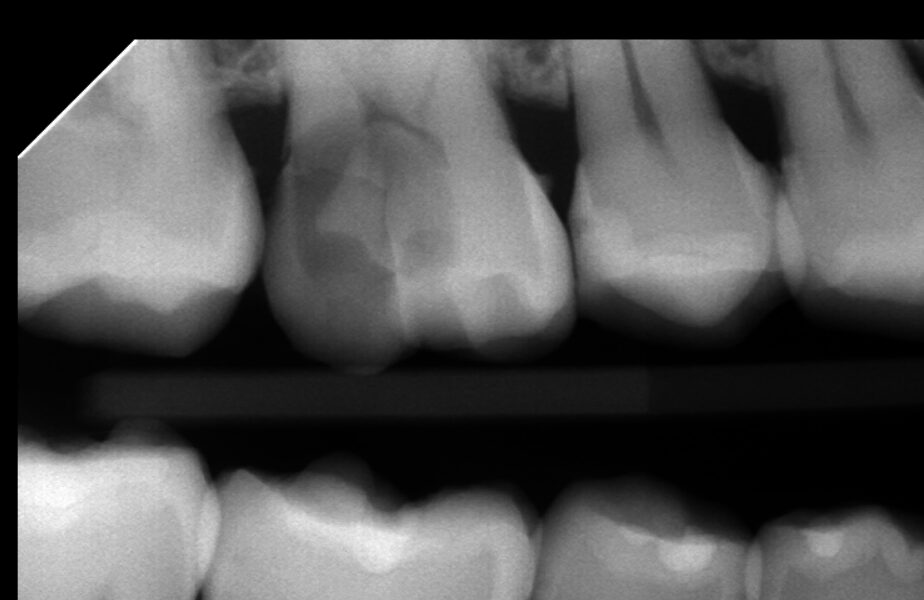

お久しぶりの歯医者さん、歯が欠けたとのことで来院、レントゲン検査にて右上奥歯に神経に達する大きな虫歯が見つかりました。

自発痛なく冷水痛が若干ある程度であったため、歯髄電気診を行なったところ神経が生きていることが確認できました。VPT歯髄温存療法の適応と判断し、ご本人様にその旨をお伝えしたところ、神経を残せる可能性があるなら試したいとのことでこの度VPT治療を行いました。